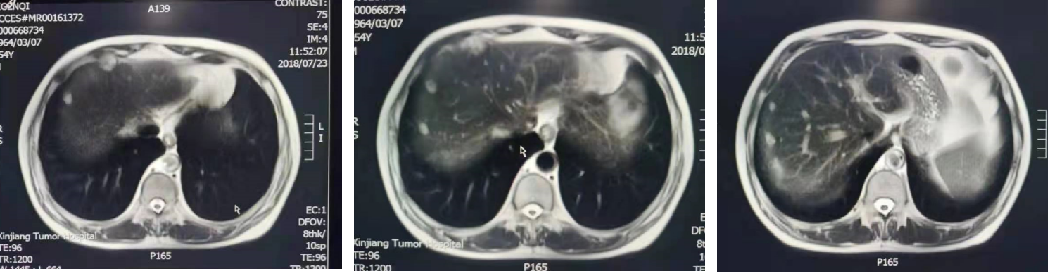

2018-07-24 肝MRI:

1.肝S4-8段边缘处多发结节,与前片(2018-05-25)比较,部分体积较前略增大,考虑转移瘤较不典型血管瘤可能性大,建议随访;2.肝S5、S6小结节,转移待排,建议随访。